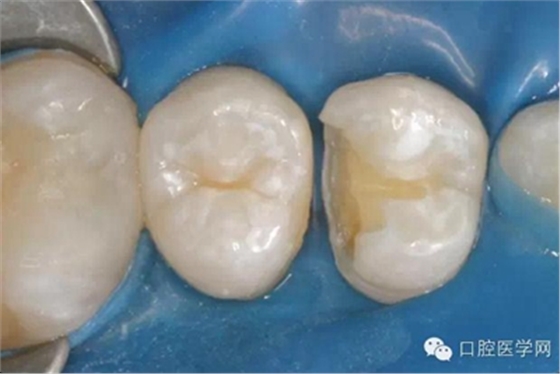

在根管治療之前我們要做麻醉,所以整個治療的過程是不疼的。治療過程中要使用橡皮障,只露出要治療的牙齒,口腔其他部分都在橡皮障之下,可以隔開唾液,因?yàn)橥僖豪镆彩怯屑?xì)菌的,如果一邊清理,一遍有唾液流到根管內(nèi)部,那么就無法做到完全無菌。同時,有橡皮障的隔絕作用,可以防止治療器械掉到嗓子里,這一點(diǎn)非常重要。